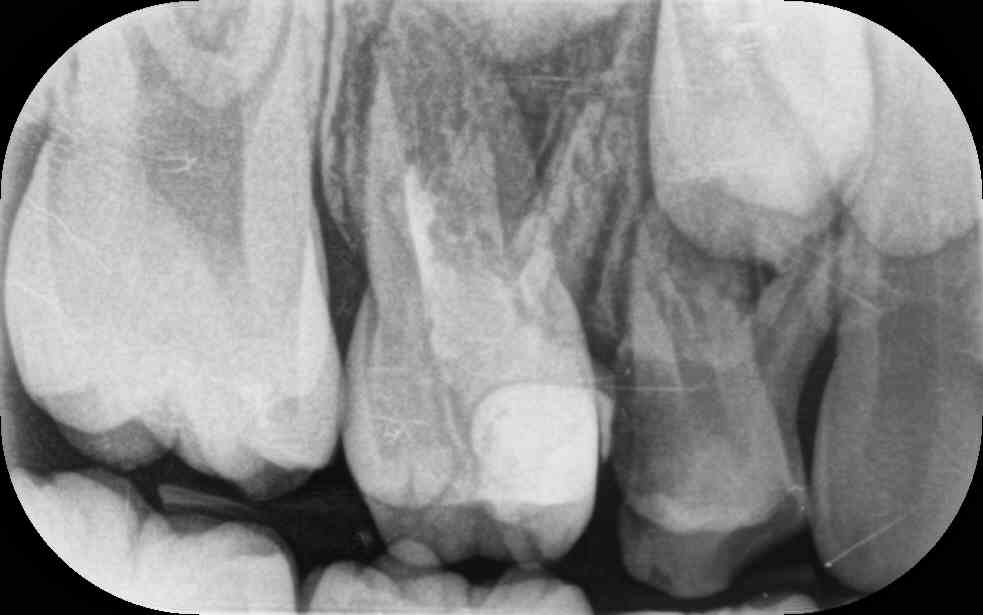

My daughter is 7 and hav deep cavity I took her to dentist one said she need 1 extraction and when I went to pediatric dentist she said she needs 4 extractions which she is going to do altogether same day I am attaching her xrays can any dentist plz advise after looking at the xrays thanks

Her both upper D are definitely for extraction and for her E need to evaluate clinically as well there might get b some Endodontic treatment and space maintainers afterwards

After extraction she will need space maintainer to keep first molar in its place so better to go for RCT to keep this tooth till age 12